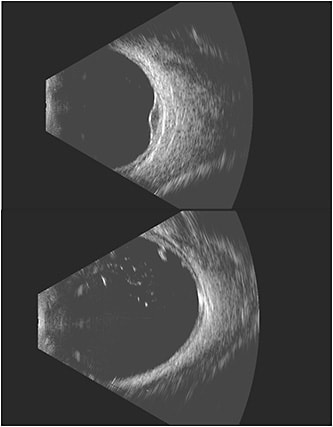

“The ability to choose between the 12 MHz and 18 MHz probe allows for better tailoring of imaging depending on the suspected diagnosis,” Dr. Fuller says (Figure 1). For example, sometimes with choroidal melanoma it is difficult to tell whether there is extraocular extension of the tumor. “The additional resolution can aid in surgical planning for plaque brachytherapy and allow for more appropriate and informed patient counseling.”

According to Timothy Fuller, MD, ocular oncologist and medical retina specialist with Texas Retina Associates in Dallas, Texas, the device’s most compelling advantage is its higher resolution. “The ability to better differentiate between the layers of the eye, including the sclera, choroid, retina, and vitreous, helps to make a timely diagnosis,” he says.

Eye Prime’s applications are similar to those of other ophthalmic ultrasound systems. “If you can’t use light to see into the eye, then sound via ultrasound is required,” London says. Eye Prime offers a more precise look at various ocular conditions. A study of a choroidal tumor with the 18 MHz probe will allow an oncologist to discern the layers, from a potential overlying retinal detachment down to the inner sclera, where extraocular extension may occur, London says. Determining whether a lesion has metastasized to the extraocular muscles or optic nerve is evident with the instrument’s high resolution. Details in the vitreous, exquisite separation of vitreous from the retina, and blood flow within a tumor can be visualized with ease. The anterior transducers will also allow a retina surgeon or oncologist to image the iris or ciliary body lesions and their extent beyond the iris, which is unseen by OCT. Another anterior application for a retina practice is the ability to image a displaced intraocular lens, which may cause hyphema in the anterior chamber.